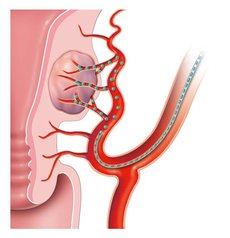

Bei der Embolisation wird über die Leiste ein sehr dünner Schlauch (Katheter) in die Arterie eingeführt und unter Röntgenkontrolle von einem spezialisierten Radiologen bis zur Gebärmutterarterie vorgebracht. Dort werden feinste Kügelchen (Microsphären) in die Myome gespritzt, so dass diese absterben und die Beschwerden verschwinden. Die Gebärmutter selbst bleibt erhalten.